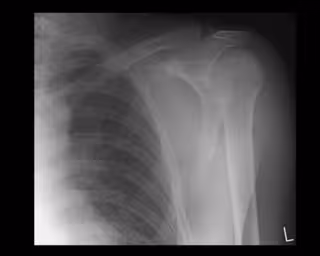

Diseñan una nano-malla con células madre para regenerar los tendones del manguito rotador

Hombro

GETTY